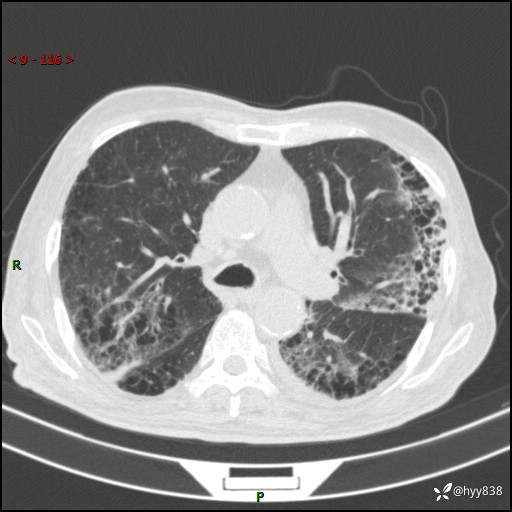

老年男性,间断咳嗽咳痰20余年,加重伴发热1天。呼吸科疑难病例讨论---结果公布

主诉:间断咳嗽咳痰20余年,加重伴发热1天

简要病史:家属代诉患者于20余年前无明显诱因出现咳嗽咳痰,痰为白色泡沫状,未行特殊治疗,不伴胸痛、胸闷、气喘、咳血等不适,1天前上午患者无明显出现发热,查体温39℃,伴咳嗽,咳痰无力,自行予以物理降温对症治疗,今晨2点左右再次出现发热,体温达40℃,自行服用复方氨酚烷胺对症治疗,凌晨3点左右复测体温38.2℃,现患者为求进一步诊治于今日就诊于我院门诊,行胸部CT提示双肺感染,遂以“肺部感染”收入我科。 患者本次起病来精神、食欲、睡眠欠佳,体力下降,体重无明显变化。

辅助检查:CT

胸部CT平扫